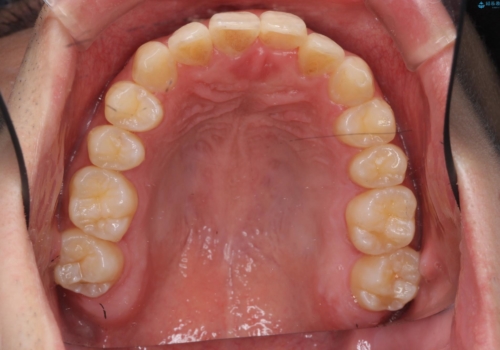

残りは全て天然歯になり、人工物の心配をしなくて済むようになりました。

治療も順調に進み、リファインメントも1回のみで済んでいます。

ブラックトライアングルも少なめで、短期間でしっかり並びました。

上の前歯のガタガタも、わずかに歯を削って並べていますので、出っ歯になったりしないようにしています。